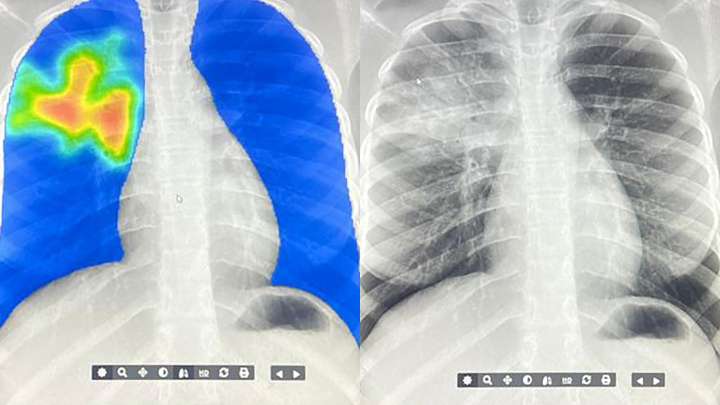

The difference? A mobile x-ray machine and an AI algorithm are detecting TB. (In case you're not familiar with AI terminology — this is basically a computer program trained on a whole lot of data.)